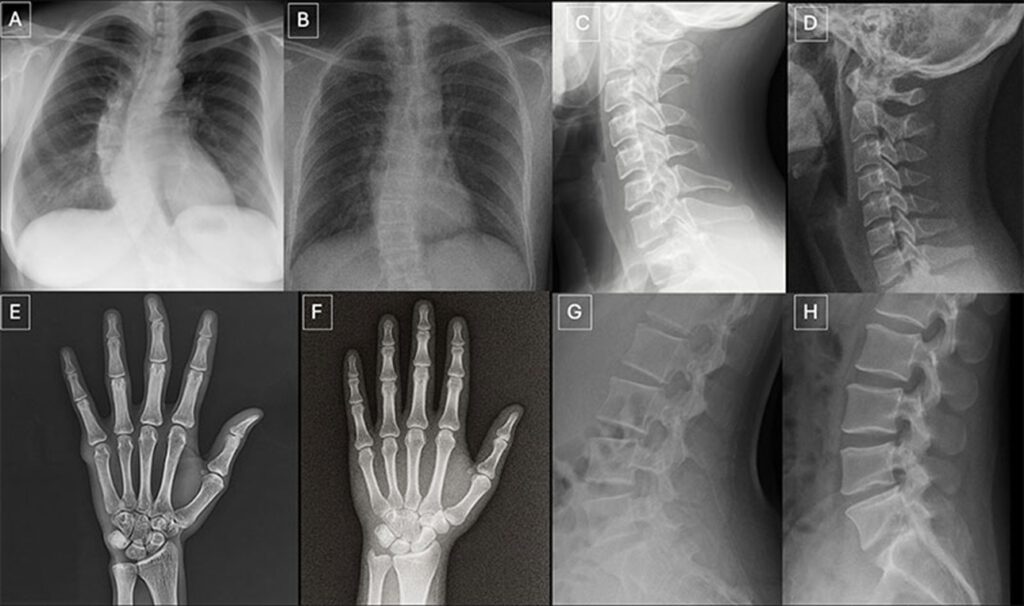

Im Vergleich sind jeweils links die echten und rechts die von GPT-4o erzeugten Röntgenbilder zu sehen – von Brustkorb, Halswirbelsäule, Hand und Lendenwirbelsäule.

Im Vergleich sind jeweils links die echten und rechts die von GPT-4o erzeugten Röntgenbilder zu sehen – von Brustkorb, Halswirbelsäule, Hand und Lendenwirbelsäule. © RSNA 2026

Die Studie arbeitete mit zwei getrennten Bilddatensätzen. Einer enthielt Aufnahmen aus verschiedenen Körperregionen, erstellt unter anderem mit GPT-4o. Der zweite konzentrierte sich auf Röntgenbilder des Brustkorbs. Diese wurden zur Hälfte mit dem offenen Modell RoentGen erzeugt.